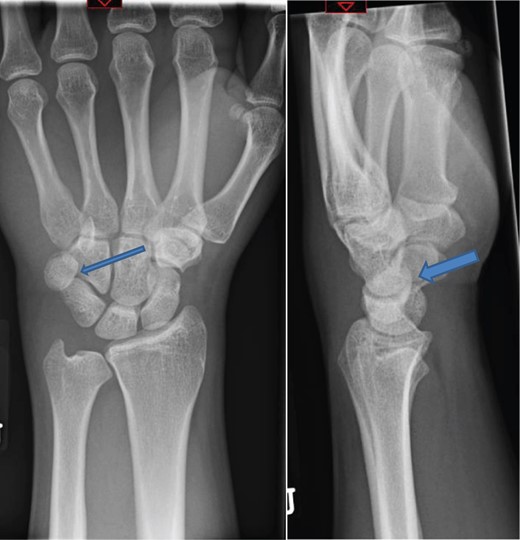

The X-rays of the patient was later reviewed by the duty radiologist and reported as a suspected dislocation of the pisiform bone, Fig. 1. Therefore the patient was recalled to the trauma clinic after three days. He was reassessed and a further three dimensional scan of the wrist was arranged. The CT scan demonstrated distal dislocation of the pisiform which appeared to lie in a ‘locked’ position beyond the distal triquetrum, Fig. 2.